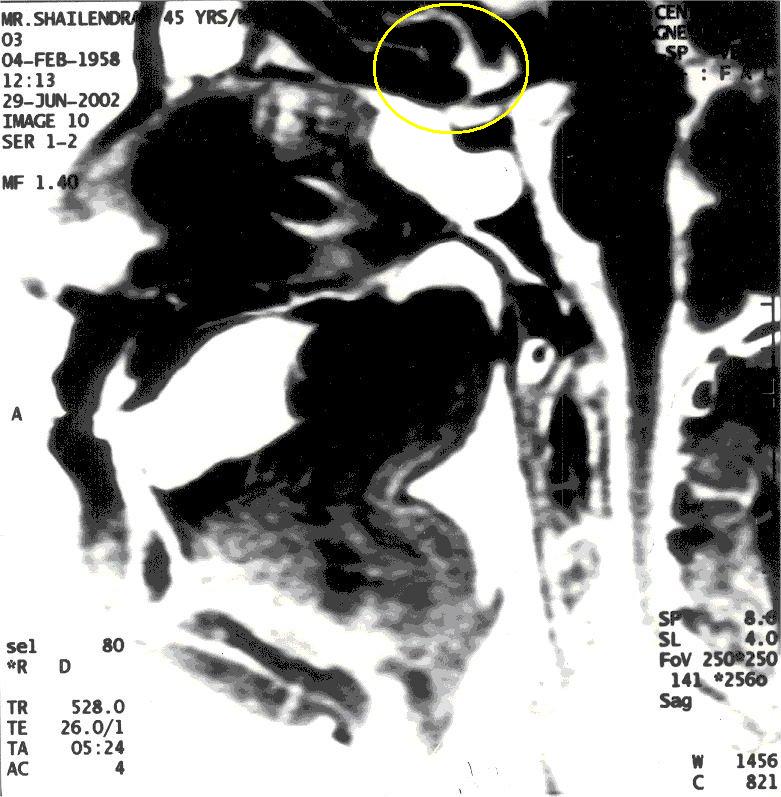

MRI of Yogiraj Shailendra Sharma in Khechari Mudra

With Khechari Mudra, notice the formation of an 'Om' like impression (highlighted in yellow)